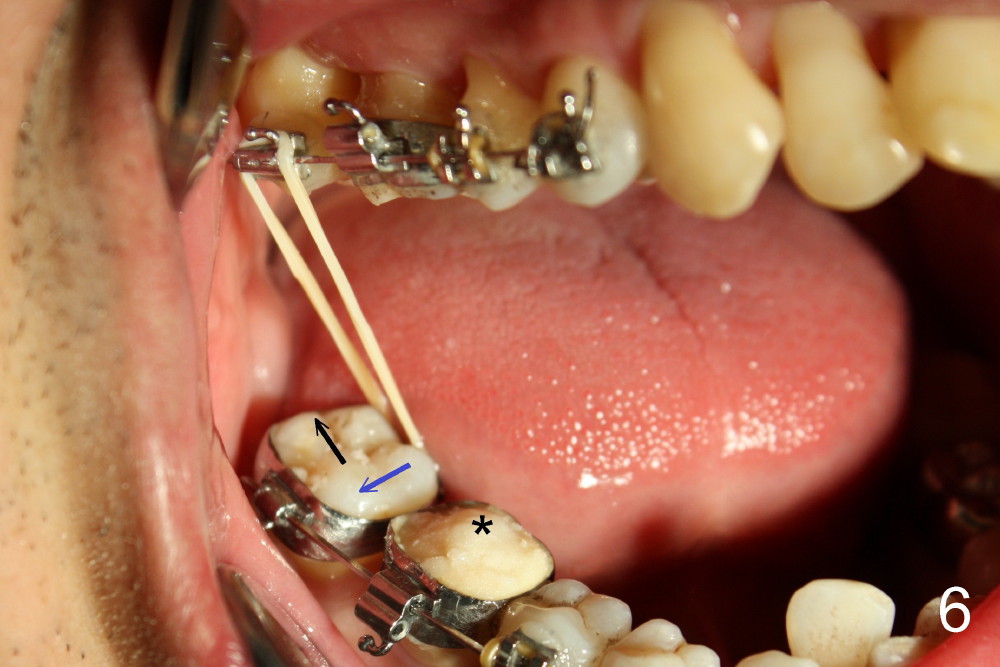

A molar band is placed for #31 and a bracket for #2 (Fig.5). A temporary crown (#30) is cemented with an intention to raise the occlusion. Notice the space between upper and lower premolars (between 2 arrowheads). There is also a space between #2 and 31. One to three elastic bands are placed between the buccal hook of #2 and the lingual cleat of #31 (Fig.5,6). One months passes without correction of the molar cross bite. More bands and brackets are placed in the upper and lower right posterior sextants (Fig.6). With combination action of elastics and segmental wires, the inclination of the tooth #31 is not only corrected buccolingually (blue arrow), but also mesiodistally (black arrow, uprighting). The implant crown is mainly used as an occlusal stop; because of constant wear, composite is being added (*) to its occlusal surface of the temporary crown to keep posterior occlusion open (let #2 and 31 move freely). In this case the implant is in fact not used as a pure anchorage to distalize #31 due to difficulty in placing an open coil spring between #30 and 31 tubes. The alignment of the upper right sextant improves under the tension (bending) of the wire (Fig.7 white arrowhead). The tooth #2 is being moved lingually. In fact, elastics are also placed between #3 lingual cleat (yellow arrowhead) and #30 buccal hook to improve #3 buccolingual position and/or inclination (compare Fig.4 and 7).